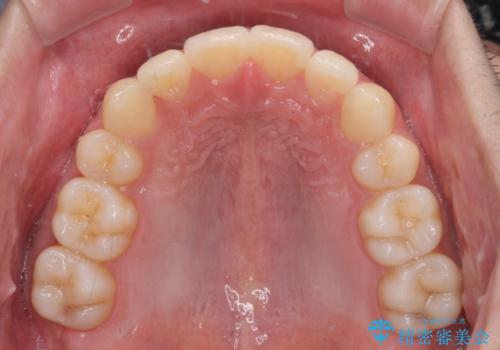

矯正治療の後戻りをインビザライン・ライトで解消

- 矯正治療の後戻りを気にして来院された患者様です。

後戻りは軽微であったので、インビザライン・ライトにより矯正治療を行うこととしました。

インビザライン・ライトは提供されるマウスピースの数に制限があり、通常のタイプよりもマウスピース提供期間が短くなっている一方、安価に治療を行うことができるプランです。

治療のゴールも変更できないため、軽微な歯列不正や、後戻り改善などに適しています。

矯正治療後は、再度後戻りすることを極力回避するために、下顎前歯の舌側を細いワイヤーを用いて保定することとしました。